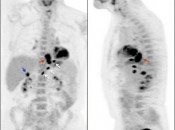

- Maximum Intensity Projection (MIP)

- Fusion of Images

3. Excellent Views: The MIP, Coronal & Sagittal Images

- 3-D Rotating MIP & Coronal “Quick MIP”

- Coronal PET

- Sagittal PET